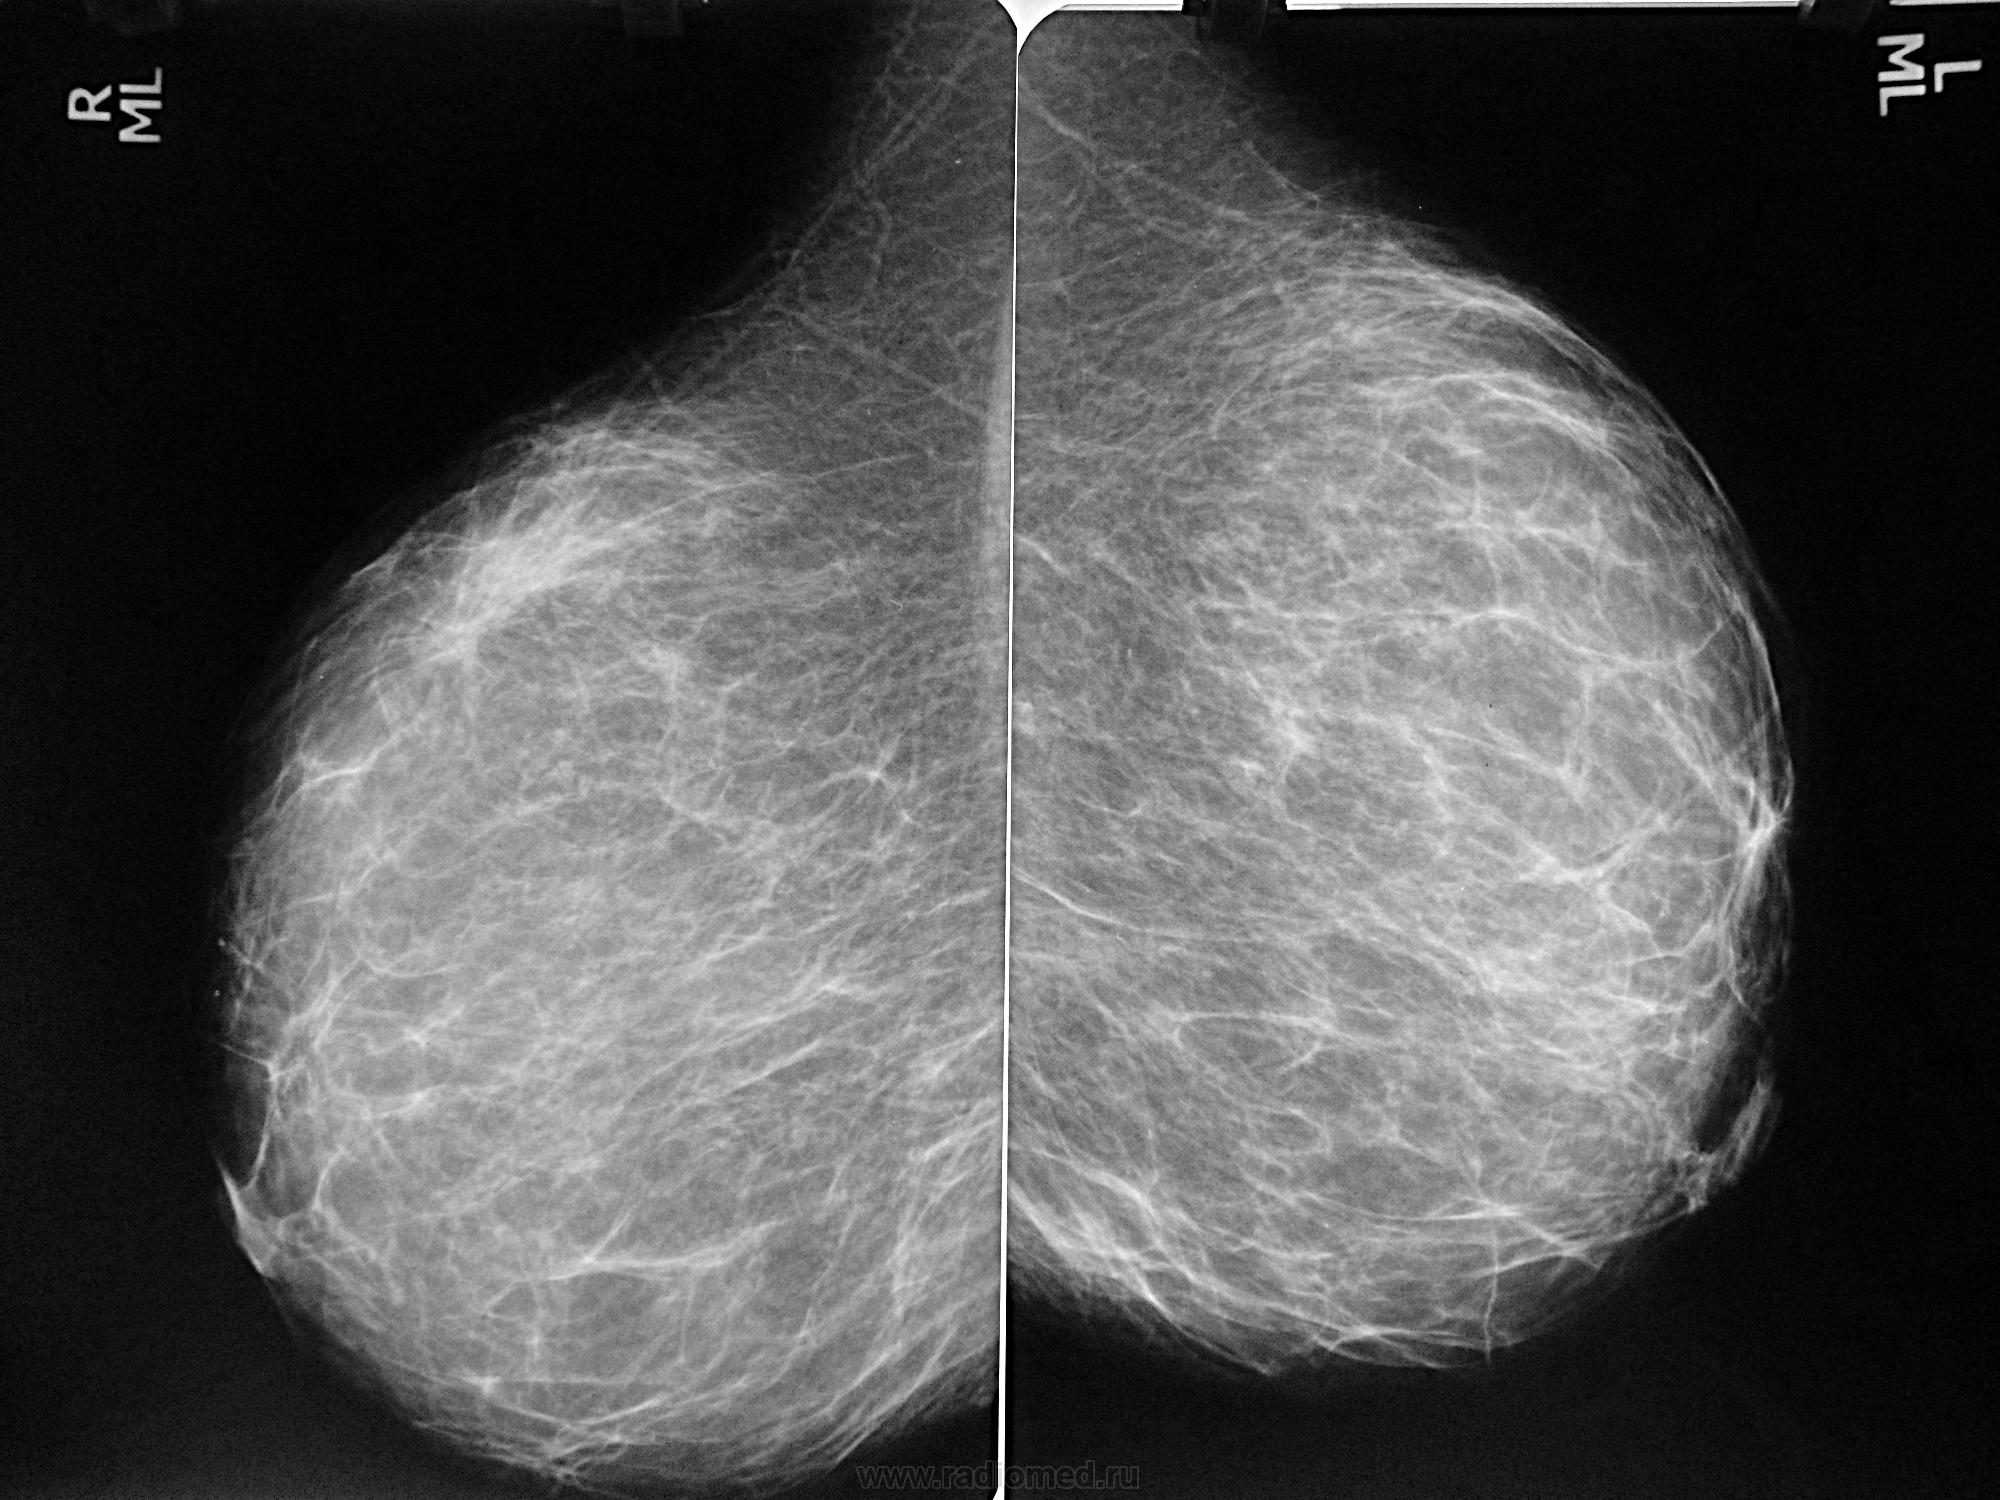

Что такое маммография: важность, процесс и результаты

Раздел: Необычные решения